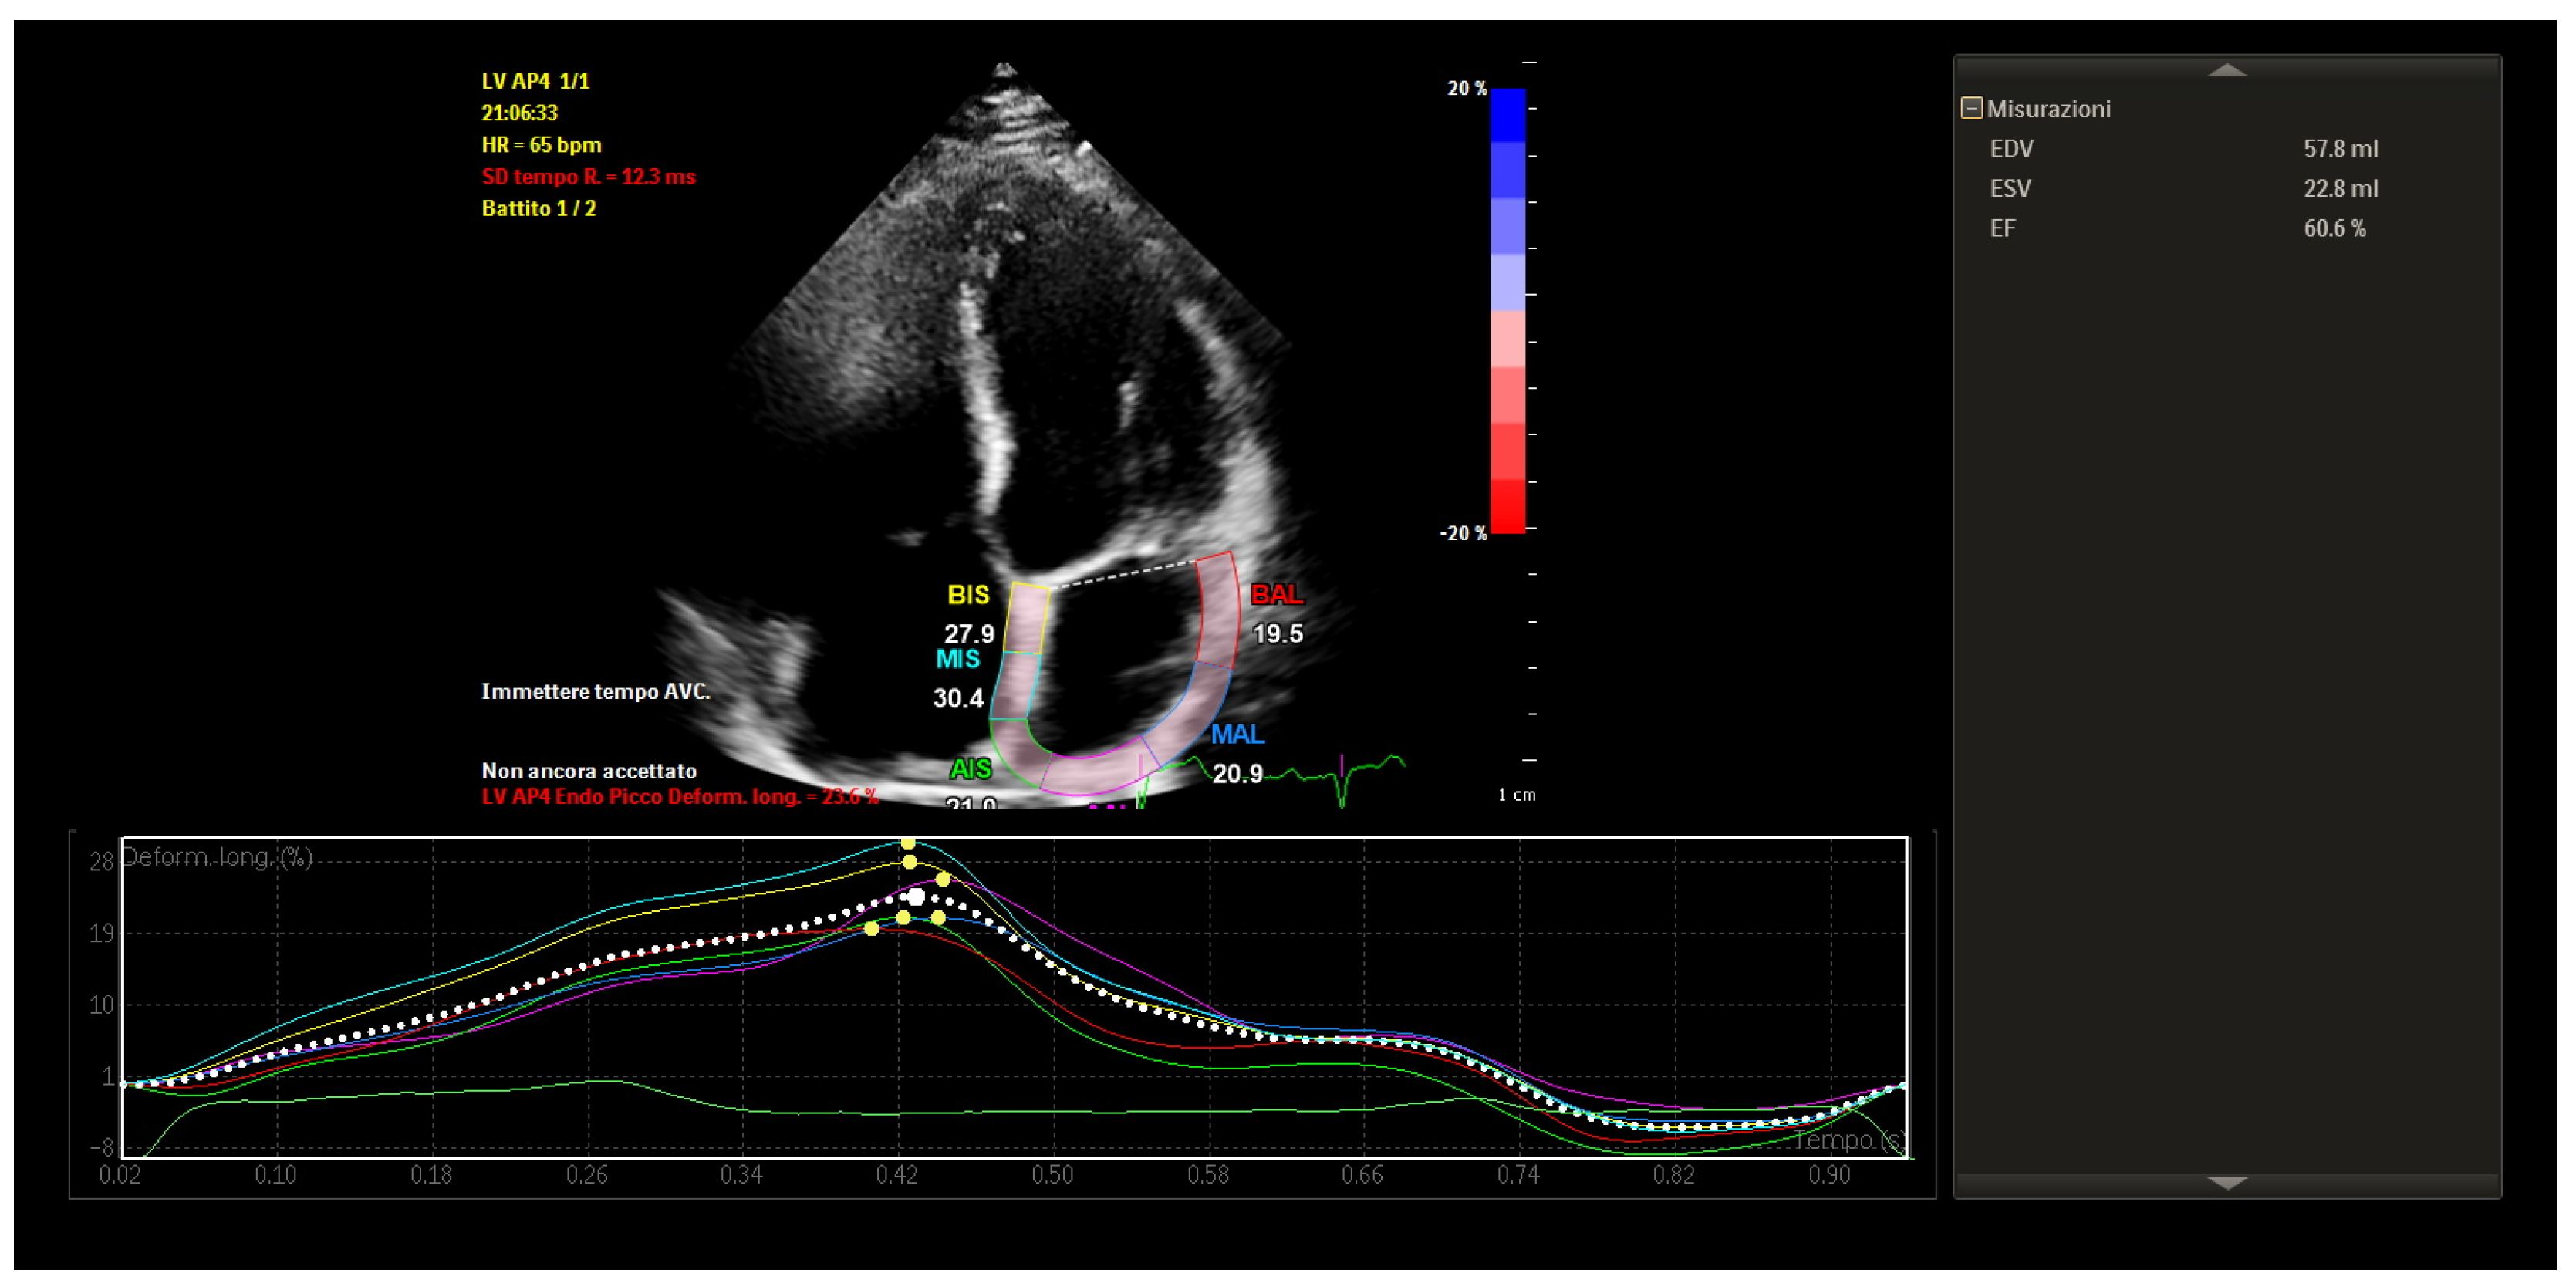

STE revealed mildly reduced left atrial longitudinal strain values, particularly in posterior and septal segments. Despite this, global atrial strain remained within functional thresholds. Importantly, the strain curves demonstrated preserved synchrony across atrial segments, with uniform timing of peak contraction and no evidence of mechanical dispersion.

These findings indicated that, although some subclinical impairment of atrial compliance was present, the atrial contractile function was globally coordinated and electromechanically integrated (Figure 4).

Figure 4. Speckle-tracking echocardiography showing mildly reduced atrial strain with preserved mechanical synchrony.